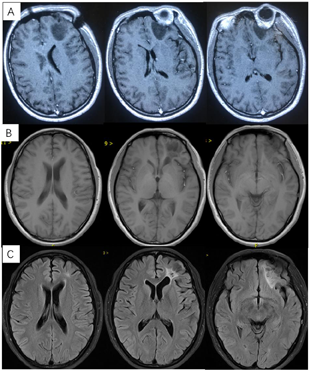

患者20年前患者体检时发现颅内占位性病变,行伽玛刀治疗,间断复查,病情稳定(图1)。20天前患者无明显诱因出现抽搐一次,伴意识丧失,持续约15分钟后逐渐恢复,至我院门诊行MR示"左侧额叶占位性病变",门诊以"颅内占位性病变"收治入院。

入院体格检查:T:36.8℃,P:69次/min,R:19次/min,BP:125/88 mmHg。专科体格检查:神志清楚,对答切题。双侧瞳孔等大等圆,直径约3 mm,对光反射灵敏。四肢肌力肌张力正常。生理反射存在,病理征阴性。既往无特殊病史。辅助检查:我院门诊MR示左额叶占位性病变(图2),倾向于高级别胶质瘤。

术后3周患者就诊于头颈肿瘤放化疗科,专科查体:左眼睑下垂,神清,言语清晰,伸舌居中,双侧瞳孔等大等圆,对光反射存在,四肢感觉活动可,肌力肌张力正常。2017年7月MR(图4)示左额叶术后改变伴出血,病灶内侧部分考虑肿瘤残留可能。为了更好地评估术后残留病变范围和制定放疗计划,患者行11C-MET PET/CT检查(图5A-D),结果示左侧脑室前角旁-左侧基底节区团块状稍高密度影,蛋氨酸代谢异常增高,考虑肿瘤残留。参照2016 ESTRO-ACROP指南[1],继发性胶质母细胞瘤放疗GTV靶区需包含术腔、T1增强上的强化区域及T2 FLAIR上的高信号区域,术后PET/CT显像所示的氨基酸代谢活跃病灶被包含在GTV之内(图5E)。患者于2017年7月始行左额叶病灶放疗(PTV 60Gy/30F,同步口服替莫唑胺化疗75mg/m2,qd)。结束后复查PET/CT(图5F-I)示病变范围明显缩小,代谢程度较前减低,左额叶少许病变存活,遂对残留病灶局部放疗加量(GTV如图5J,6Gy/3F)。放疗过程顺利,期间出现Ⅲ°白细胞减低,予以升白细胞治疗后好转出院。后于2017年10月起口服替莫唑胺辅助化疗(150~200mg/m2,d1-d5,q28d),期间规律复查。